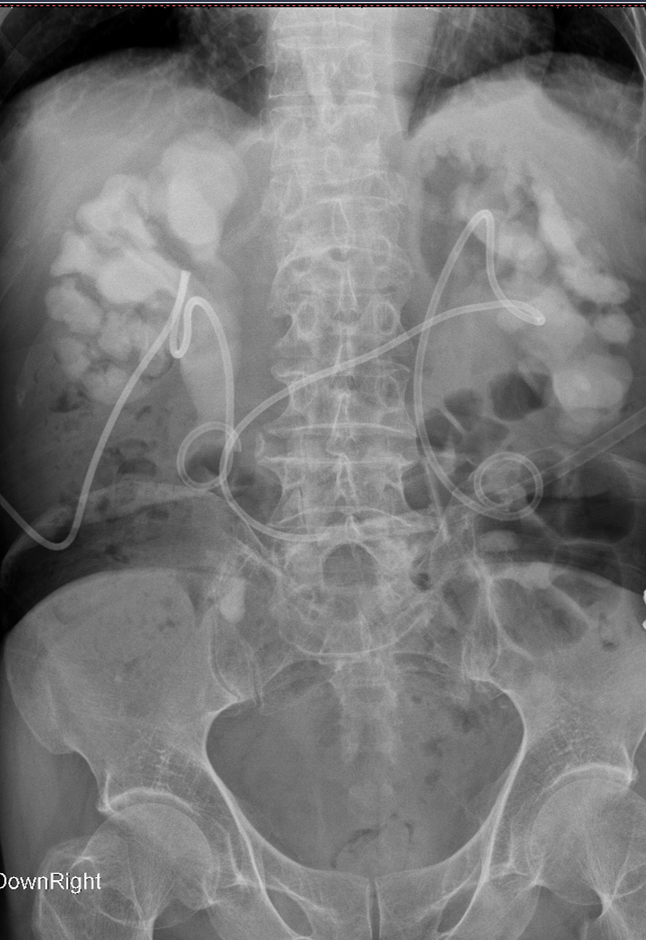

术后KUB见双肾造瘘管,及双侧内支架管固定妥善

正常人输尿管长约25cm左右,该患者输尿管迂曲扩张,长达35-40cm左右,裁剪部分输尿管成型